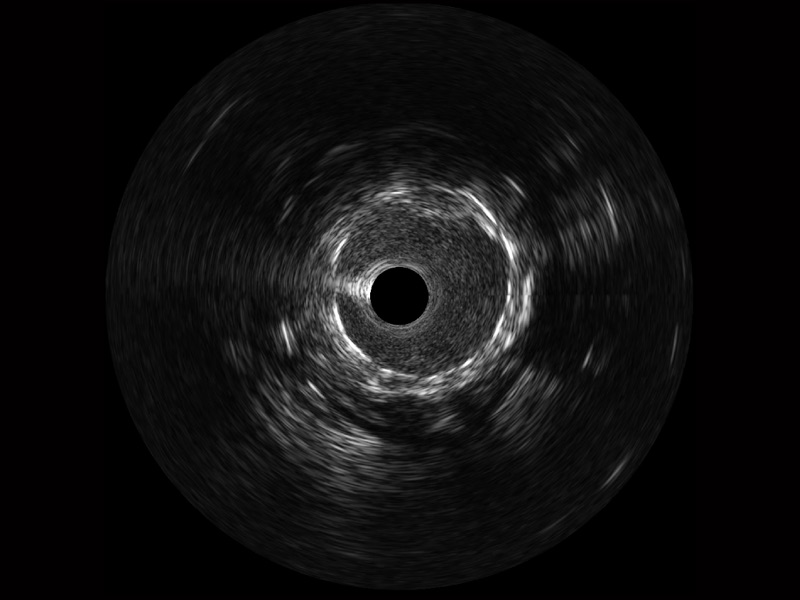

传统IVUS图像

对比传统IVUS导管成像,乐玩lewin国际宽频IVUS图像的近场支架梁显影更细腻,远场中膜外血管仍清晰可辨,兼顾远中近,兼顾分辨力与穿透深度